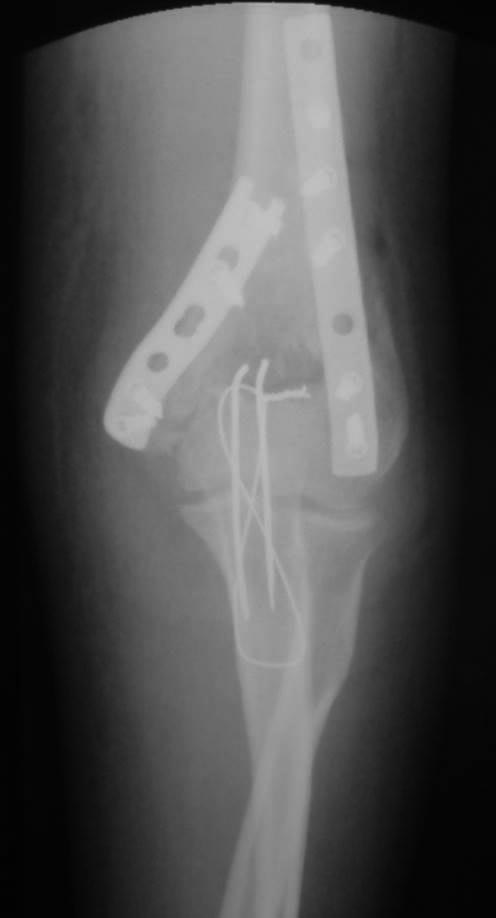

[Ortho] Перелом плечевой и головки лучевой костей (и немного локтевой)

Как обещал, выкладываю послеоперационные (на следующий день после

операции) фото. Заранее прошу слишком проксимальную остеотомию локтевого

отростка не ругать. Обычно делаю дистальнее.